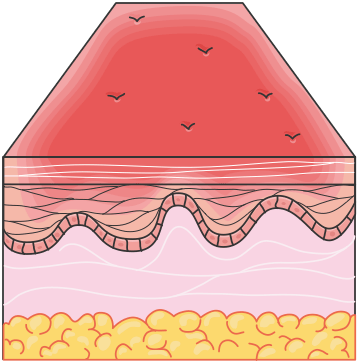

First-Degree Burns: These are superficial burns affecting only the epidermis. They present with erythema, mild swelling, and pain. First-degree burns typically heal within 3 to 7 days without scarring. An example of a first-degree burn is a mild sunburn.

Figure 1.21, generated using Servier Medical Art, provided by Servier, licensed under a Creative Commons Attribution 4.0 unported license